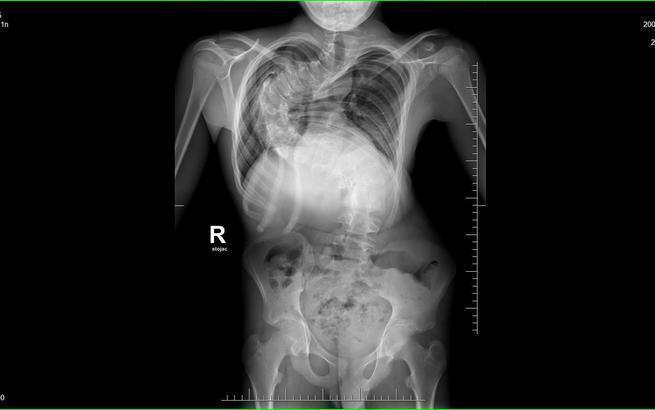

Alan od września ma rozpocząć naukę w szkole ponadpodstawowej. Chciałby żyć tak jak rówieśnicy. Skrzywienie, co widać na zdjęciu RTG, jest ekstremalne, wymaga pilnej korekcji. Trzeba jak najszybciej zebrać fundusze na leczenie operacyjne. Bez Was nie damy sobie sami rady...

Wielu specjalistów, mnóstwo różnych sposobów leczenia, aż wreszcie informacja, że w Polsce nie ma dla niego ratunku. Mamy to napisane na oficjalnym dokumencie medycznym z pieczątką i podpisem. To nie jest żaden wymysł, czy inna fanaberia. Najbliższym miejscem, gdzie mogą pomóc Alanowi, jest czeska klinika w Brnie. Wiąże to się jednak z ogromnym wydatkiem, a nasz wniosek o dofinansowanie z NFZ przepadł. Dlatego musimy prosić Was o pomoc... Jego kręgosłup jest już wygięty o ponad 140 stopni...

Skrzywiony kręgosłup niesie za sobą całe mnóstwo dalszych komplikacji. Oprócz bólu i wstydu z powodu dziwnego wyglądu chory cierpi również przez nacisk na narządy wewnętrzne, takie jak płuca czy serce. Co gorsza, wada cały czas się pogłębia, a Alan przecież cały czas rośnie. Nie wiemy, jak długo jeszcze wytrzyma, a nieprzespane ze strachu noce stały się naszą przykrą codziennością.

Mój syn ma 15 lat, a ja modlę się, by jak najszybciej udało się go uwolnić od koszmaru, jakim jest skolioza. Operacja jest pilnie potrzebna, a w Polsce nie ma ośrodka, który mógłby się podjąć skutecznego i bezpiecznego leczenia operacyjnego. Szansą dla Alana jest operacja przeprowadzona przez profesora Martina Repko w Brnie w Czechach. Koszt takiego zabiegu przekracza nasze możliwości finansowe, a po operacji trzeba wrócić specjalistycznym transportem medycznym.